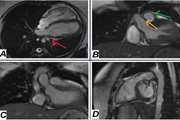

ترومبوز قلبی: زنگ خطری برای پارگی قلب

در بیماران سکته قلبی، تشکیل لخته در نوک چپ قلب می‌تواند نشانه اولیه یک عارضه خطرناک به نام پسودوآنوریسم (کیسه کاذب قلب) باشد که ممکن است منجر به پارگی شود. پزشکان توصیه می‌کنند این بیماران را با تصویربرداری منظم پیگیری کنید تا از بروز فاجعه جلوگیری شود.